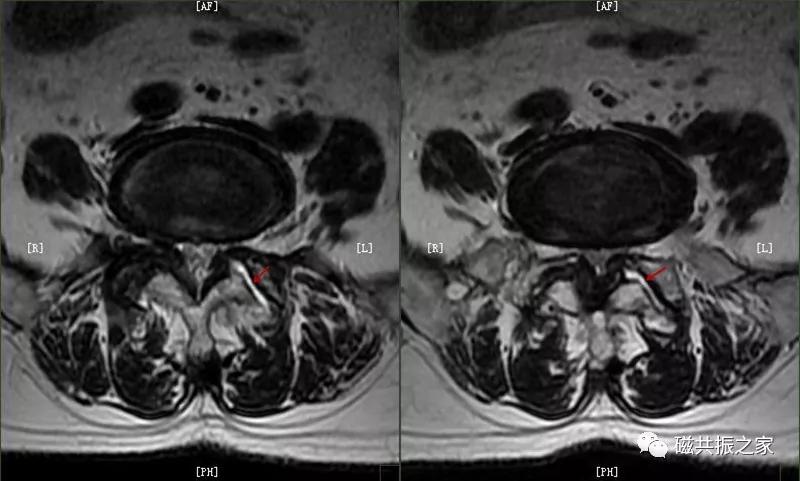

4.小关节积液

主要表现:小关节间隙液量增多,常伴随长期腰痛。